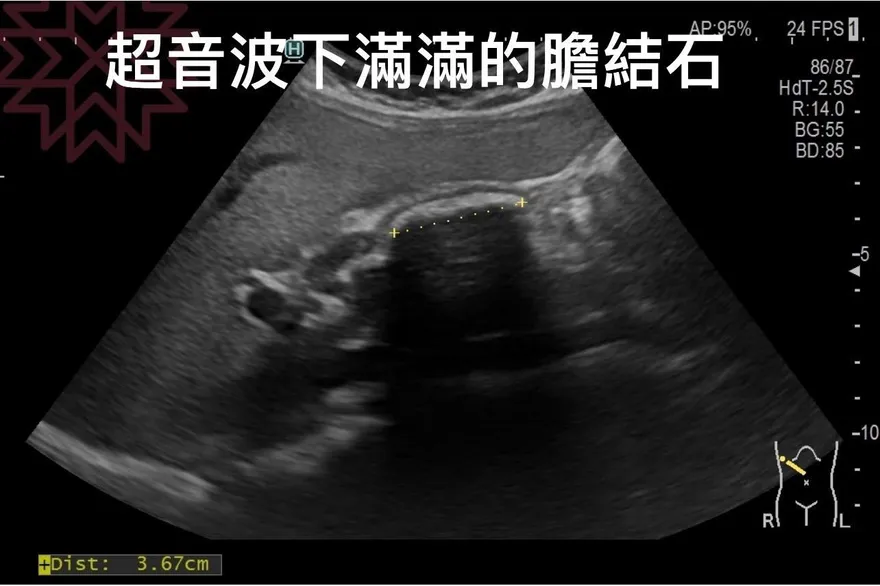

結石

膽結石